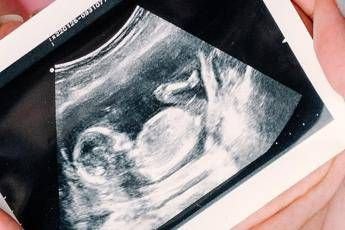

Gravidanza, arrivano le nuove linee guida dell’Iss: ecco quando fare e quando non fare l’ecografia e altri esami

Sì all'ecografia nel primo trimestre per individuare precocemente eventuali malformazioni fetali, oltre a quella già raccomandata nel secondo trimestre. Sì anche all'offerta dello screening nel primo trimestre delle anomalie cromosomiche più frequenti, tra cui la sindrome di Down, mediante test combinato o test del Dna fetale, da proporre a tutte le donne indipendentemente dall'età. Raccomandata l'esecuzione della misura della distanza tra fondo dell'utero e sinfisi pubica ad ogni bilancio di salute a partire dalle 24 settimane gestazionali per valutare l'accrescimento fetale. Rimane non raccomandata l'ecografia nel terzo trimestre, salvo specifica indicazione clinica. Sono queste le principali novità introdotte dalla terza parte dell'aggiornamento della linea guida 'Gravidanza fisiologica', presentata durante un webinar a cura dell'Istituto superiore si sanità, al quale si sono iscritti 850 professionisti sanitari. Il documento è stato sviluppato dal Centro nazionale per la prevenzione delle malattie e la promozione della salute (Cnapps) dell'Iss, nell'ambito delle attività del Sistema nazionale linee guida (Snlg). La possibilità di individuare già nel primo trimestre eventuali malformazioni consente alla donna e al partner di prepararsi consapevolmente alla nascita, valutare eventuali terapie intrauterine, programmare il parto in strutture adeguate alle necessità assistenziali neonatali o decidere per una interruzione volontaria della gravidanza, spiega l'Iss. "L'ecografia è uno strumento straordinario che ha rivoluzionato l'assistenza ostetrica. Tuttavia, non tutto ciò che è tecnicamente possibile è clinicamente appropriato e non tutto ciò che rassicura è realmente necessario", afferma Serena Donati, responsabile scientifica dell'aggiornamento. "In Italia si eseguono in media 6 ecografie in gravidanza, senza differenze tra gravidanze fisiologiche e patologiche: ben oltre quelle raccomandate dalle linee guida nazionali e internazionali. Quando la pratica clinica si discosta dalle evidenze scientifiche – sottolinea – è fondamentale spiegare con chiarezza alle donne quali siano le indicazioni appropriate agli esami e, quando opportuno, avere il coraggio di dire che non sono necessari. Le linee guida rappresentano una bussola istituzionale per garantire qualità dell'assistenza, equità di accesso alle cure e sostenibilità del Servizio sanitario nazionale". Tra le principali novità dell'aggiornamento, la linea guida: raccomanda l'ecografia del primo trimestre per la diagnosi precoce di malformazioni fetali e per una corretta datazione della gravidanza; conferma l'offerta universale dello screening nel primo trimestre delle anomalie cromosomiche più comuni, introducendo l’esame del Dna fetale; sottolinea l'importanza del counselling, per rispondere in modo completo e trasparente ai bisogni informativi delle donne rispetto agli accertamenti per anomalie congenite; ribadisce il valore della percezione dei movimenti fetali come indicatore del benessere del feto; raccomanda la misurazione della lunghezza fondo-sinfisi come monitoraggio per la crescita fetale dopo la 24esima settimana; raccomanda di limitare ai soli casi con indicazione clinica l'ecografia per la valutazione della crescita fetale nel terzo trimestre.  L'obiettivo del nuovo aggiornamento – chiarisce l'Iss – è offrire ai professionisti uno strumento completo, facile da consultare, in cui il collegamento tra prove scientifiche e raccomandazioni risulti esplicito e tracciabile. Il documento definisce indicazioni, limiti, requisiti formativi e implicazioni organizzative dei diversi interventi di screening basati sull'ecografia, con l'obiettivo di ridurre la variabilità ingiustificata e contrastare indicazioni inappropriate. Il Sistema nazionale linee guida dell'Iss – evidenzia una nota – ha il ruolo di garante metodologico e di governance nazionale del processo di produzione di linee guida di buona qualità, informate dalle migliori prove disponibili e rispondenti ai bisogni di salute del Paese, sulla base di criteri di rilevanza e impatto clinico, economico e sociale. Nel 2010, il Snlg ha pubblicato la linea guida 'Gravidanza fisiologica' in cui sono stati definiti gli interventi da offrire alle donne con una gravidanza in fisiologica evoluzione.